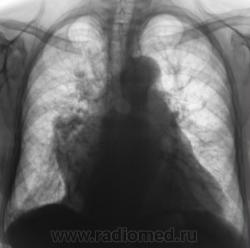

При расшифровке цифровых флюорограмм пациент "взят на контроль". Произведено стандартное исследование.

На рентгенограммах (в отличии от томо) на верхушке ничего не заметил. А так, похоже на митр. недостаточность.